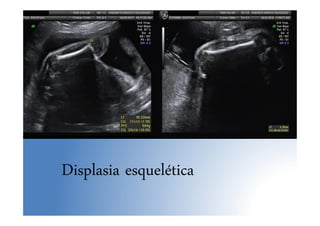

Anomalías sist. músculoesquelético

• Baja frecuencia

• Lo más importante: determinar su letalidad

• Displasia esquelética no letal más frecuente:

acondroplasia heterocigota ( se Dx en 3º T)

• Signo de alarma: Fémur corto (p<5 para EG, <

2DE)

• La mayoría de los LF cortos aislados son

constitucionales

• Displasia: LF < 4 DE. Sino: controles seriados

• Polihidramnios: signo de mal prónóstico

Displasia esquelética